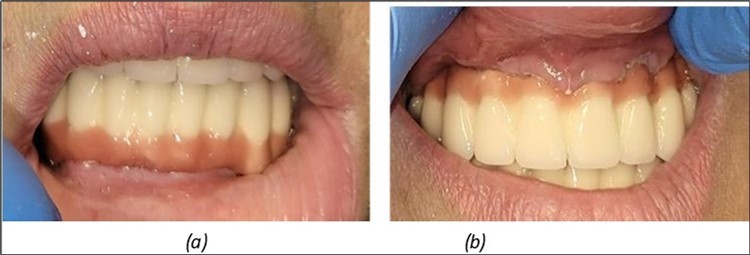

Figure 6.Definitive metal-ceramic prosthetic restoration cemented 4 days postoperatively: (a) Junction area at the mandible between the definitive metal-ceramic prosthetic restoration and the gingiva; (b) Junction area at the maxilla

Figure 7.(a) The aesthetic appearance of the patient from the front 4 days. b) 3 years after

The results of rehabilitation treatment with corticobasal and compressive implants with a polished surface after the failure of two stage implants were highlighted over a period of 3 years and 3 months as being very good (Figure 14, Figure 15), with the patient completing a satisfaction survey in this regard. Certainly, it is necessary to continuemonitoring these results in the long term.